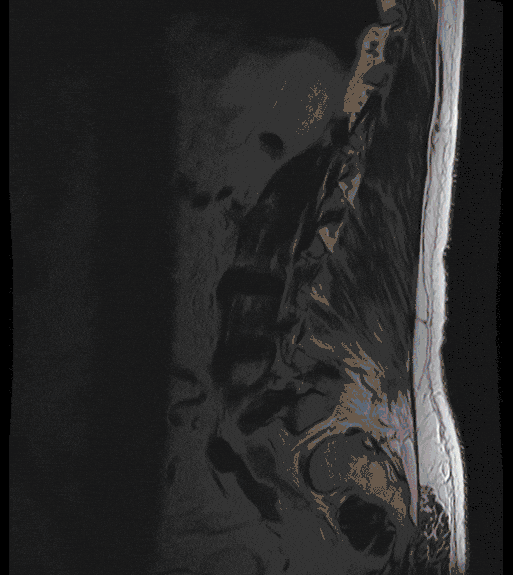

Spinal Stenosis

Narrowing of the spinal canal of the lumbar and cervical spine can lead to pain in the arms or legs, gait disturbances and restriction of walking distance.

In the case of high-grade narrowing, conservative therapy measures often fail to achieve sufficient and lasting improvement, so that surgical treatment must be considered.